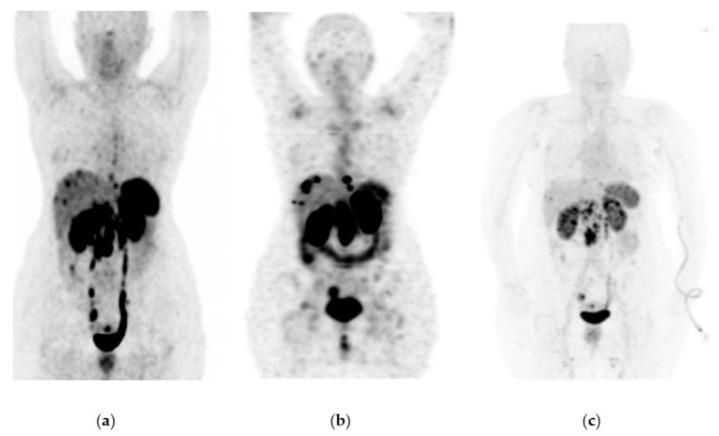

Lu-iPSMA is a novel radioligand developed at ININ-Mexico with a high affinity for the PSMA protein heavily expressed in cancer cells of approximately 95% of patients with metastatic castration-resistant prostate cancer (mCRPC). Lu-DOTATOC is a patent-free radioligand, molecularly recognized by somatostatin receptors (SSTR-2) overexpressed in cancer cells of about 80% of patients with metastatic gastroenteropancreatic neuroendocrine tumors (GEP-NET). This translational research aimed to determine the efficacy and safety of Lu-iPSMA and Lu-DOTATOC developed as GMP pharmaceutical formulations for treating progressive and advanced mCRPC and NET. One hundred and forty-five patients with mCRPC and one hundred and eighty-seven subjects with progressive NET (83% GEP-NET and 17% other NET), treated with Lu-iPSMA and Lu-DOTATOC, respectively, were evaluated. Patients received a mean dose of 7.4 GBq per administration of Lu-iPSMA (range 1-5 administrations; 394 treatment doses) or Lu-DOTATOC (range 2-8 administrations; 511 treatment doses) at intervals of 1.5-2.5 months. Efficacy was assessed by SPECT/CT or PET/CT. Results were stratified by primary tumor origin and number of doses administered. Patients with mCRPC showed overall survival (OS) of 21.7 months with decreased radiotracer tumor uptake (SUV) and PSA level in 80% and 73% of patients, respectively. In addition, a significant reduction in pain (numerical scale from 10-7 to 3-1) was observed in 88% of patients with bone metastases between one and two weeks after the second injection. In the GEP-NET population, the median progression-free survival was 34.7 months, with an OS of >44.2 months. The treatments were well tolerated. Only ten patients experienced grade ≥ 3 myelosuppression (3% of all patients). The observed safety profiles and favorable therapeutic responses demonstrated the potential of Lu-iPSMA and Lu-DOTATOC to improve overall survival and quality of life in patients with progressive and advanced mCRPC and NET.

镥-PSMA是墨西哥国立核科学研究所研发的一种新型放射性配体,对约95%的转移性去势抵抗性前列腺癌(mCRPC)患者癌细胞中高表达的PSMA蛋白具有高亲和力。镥-奥曲肽是一种无专利的放射性配体,可被约80%的转移性胃肠胰神经内分泌肿瘤(GEP-NET)患者癌细胞中过表达的生长抑素受体(SSTR-2)分子识别。这项转化研究旨在确定作为药品生产质量管理规范(GMP)制剂开发的镥-PSMA和镥-奥曲肽治疗进展期和晚期mCRPC及神经内分泌肿瘤(NET)的疗效和安全性。分别对145例mCRPC患者和187例进展期NET患者(83%为GEP-NET,17%为其他NET)进行了评估,这些患者分别接受了镥-PSMA和镥-奥曲肽治疗。患者接受镥-PSMA(范围为1至5次给药;394个治疗剂量)或镥-奥曲肽(范围为2至8次给药;511个治疗剂量),每次给药平均剂量为7.4GBq,给药间隔为1.5至2.5个月。通过单光子发射计算机断层扫描/计算机断层扫描(SPECT/CT)或正电子发射断层扫描/计算机断层扫描(PET/CT)评估疗效。结果按原发肿瘤来源和给药剂量数进行分层。mCRPC患者的总生存期(OS)为21.7个月,分别有80%和73%的患者放射性示踪剂肿瘤摄取(SUV)和前列腺特异抗原(PSA)水平降低。此外,在第二次注射后1至2周内,88%的骨转移患者疼痛显著减轻(数字评分从10 - 7降至3 - 1)。在GEP-NET人群中,无进展生存期的中位数为34.7个月,总生存期>44.2个月。这些治疗耐受性良好。只有10例患者出现≥3级骨髓抑制(占所有患者的3%)。观察到的安全性概况和良好的治疗反应表明,镥-PSMA和镥-奥曲肽有潜力改善进展期和晚期mCRPC及NET患者的总生存期和生活质量。